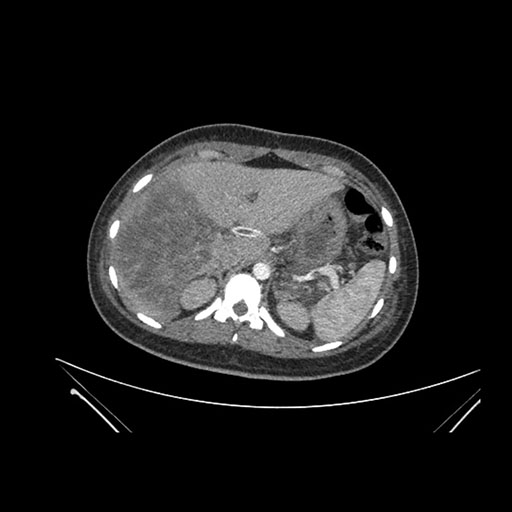

Axial Arterial